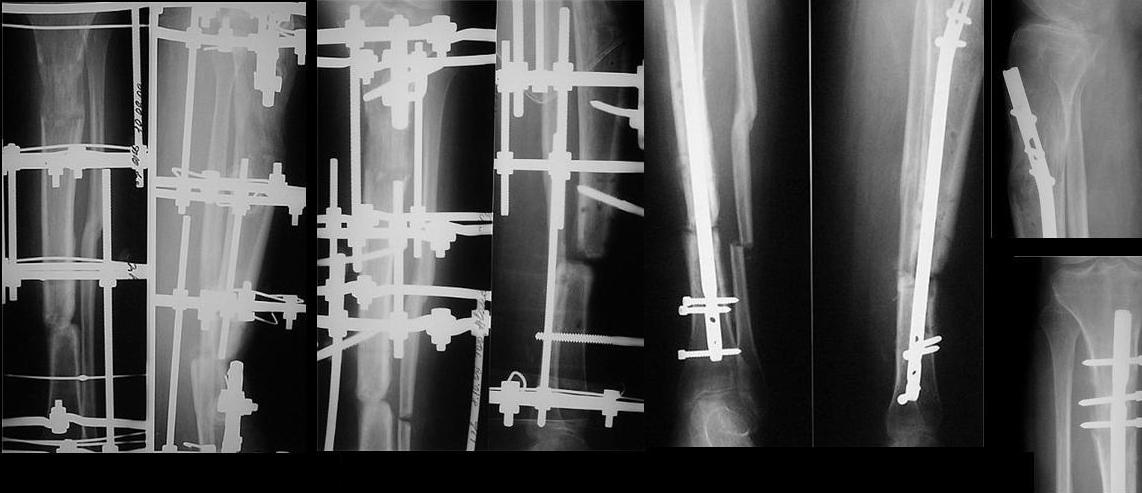

Уважаемые коллеги! Прошу совета.Больная, 32 лет, рабочая, 2,5 года назад в ДТП получила открытый перелом костей левой голени в с/3. В одной из больниц нашего города, где отдают предпочтение накостному остеосинтезу, произведен остеосинтез б/б кости пластиной с 7 отверстиями с иммобилизаций гонитной гипсовой повязкой, почему-то с эквинусной установкой стопы. В послеоперационном периоде наступил некроз кожных покровов, нагноение раны, оголение кости и пластины на протяжении 5 см. Следующие 7 месяцев идет борьба за сохранение пластины, закрытие раны (кожная пластика). Исход - несращение, остеомиелит, функционирующий свищ, миграция винтов. Пластина удалена. И уже в другом лечебном учреждении, произведена резекция концов б/б кости на протяжении 4,5 -5 см., гнойный процесс ликвидирован. Произведено успешное замещение дефекта по Илизарову. Но при стыковке отломков возникла рекурвация голени до 25 град. Все эти годы стопа оставалась в эквинусном положении, конечность не нагружалась. Имеется лимфедема, I cт. Движения в коленном суставе восстановились, а в голеностопном остались на уровне качательных. К нам больная обратилась с просьбой долечить, поскольку прежние доверительные отношения с лечащим врачом по некоторым причинам были нарушены. На голени 4-х кольцевой аппарат: на дистальном и проксимальном кольцах по 3 спицы, на средних - по одной. Аппарат стоит уже 7 мес., нестабилен, мягкие ткани вокруг некоторых спиц воспалены. Продолжить лечение имеющимся аппаратом вряд ли удастся. Наш план дальнейшего лечения: 1. снять аппарат; произвести остеотомию м/б кости, зафиксировать голень спице-стержневым АВФ, попытавшись одномоментно «выставить» ось голени 2. после заживления ран от спиц предыдущего аппарата и полного устранения рекурвации аппаратом, произвести второй этап операции - выполнить БИОС с рассверливанием костномозгового канала.Вопросы: 1. Может быть, следует обойтись только первым этапом, учитывая наличие периода нагноения, и завершить лечение АВФ? 2. Какие неожиданности БИОС технического порядка могут встретиться в данном случае и какие есть «маленькие хитрости» для их преодоления? 3. Проксимальное блокирование вероятнее всего произойдет по регенерату, будет ли оно состоятельным (регенерату около 6 мес.)? 4. Что делать со стопой? Пытаться разработать или планировать удлинение ахиллова сухожилия? Жду совета. Виктор.

Сделан первый этап операции: наложен спице-стержневой аппарат с остеотомией малоберцовой кости на уровне ложного сустава, с захватом переднего отдела стопы полукольцом с целью выведения из порочного положения.

Проксимальное кольцо на стержне Штеймана и Шанца - не будут мешать введению штифта. Дистальное - на двух спицах и стержне. Два промежуточных - по стержню на каждое. Стержни диафизарной части планируем использовать как джойстики, аппаратом дадим компрессию на штифте.

Положение отломков улучшилось. Манипулируя стержнями, в ожидании заживления ран, довправим отломки, попытаемся вывести стопу, насколько успеем. Затем выполним БИОС.

сделан первый этап операции: остеосинтез спице-стержневым аппаратом 7.11.09 г. выполнен второй этап - БИОС с рассверливанием канала, операция прошла без ожидаемых трудностей, открывать зону ложного сустава не пришлось. Прошу сделать замечания.

Виктор Попов, Караганда.

Рекурвация вроде осталась. Недорепонировали на этапе ЧКО.

И точка входа слишком низко.

И гвоздик коротковат imho.

Мы бы сделали заход через переднее межмыщелковое поле, тогда бы динамический блокирующий винт в овальном отверстии прошёл бы через нормальную кость, а не через регенерат. Ну, и стержень, соответственно, потребовался бы длиннее.